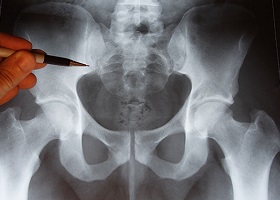

Прежде всего, необходимо разобраться в анатомии. Копчик представляет собой завершающую часть позвоночника. По сути, он является рудиментом, так как соединяется с крестцом полуподвижным суставом. У животных эта кость отвечает за движение хвоста. В ходе эволюции человек утратил хвост, но копчик остался.

Копчик состоит из нескольких хвостовых позвонков, однако в анатомии его рассматривают как единое целое. Он имеет форму, схожую с крестцом, и образует чашеобразную структуру таза человека.

Несмотря на рудиментарное происхождение, копчик выполняет важные функции. К нему прикрепляются различные мышцы, сухожилия и связки, которые формируют тазовое дно и поддерживают внутренние органы. В сидячем положении вес человека распределяется на копчик и седалищные кости.